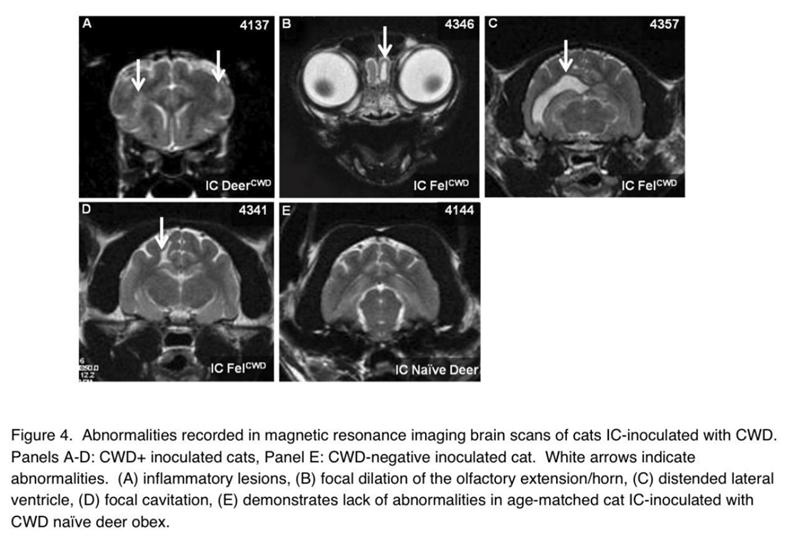

△给猫接种CWD后(A-D)的大脑影像 (图源:Susceptibility of domestic cats to chronic wasting disease)